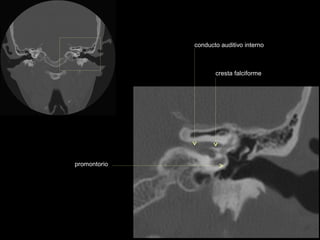

conducto auditivo interno

cresta falciforme

promontorio